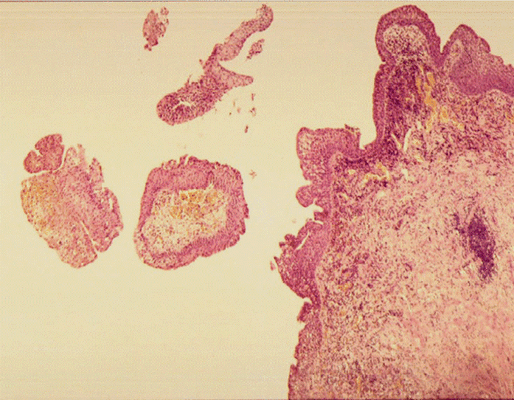

Патоморфологическое исследование пациентки К.

Морфологическая картина полипоидного цистита. Окраска гематоксилин-эозином, х5